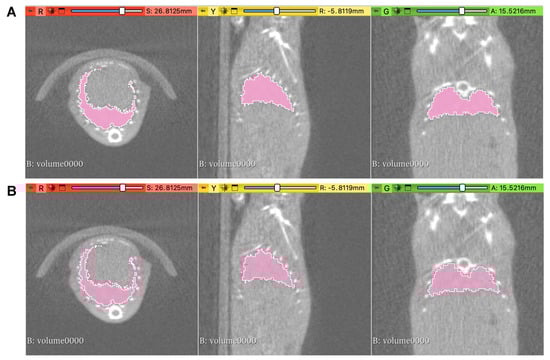

2.2. Contouring Methods

3.1. Geometry